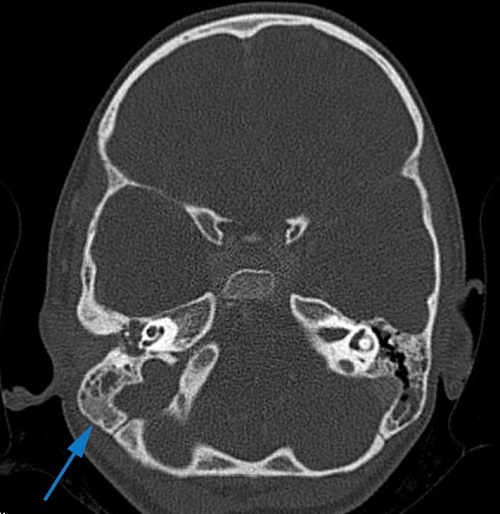

Al día siguiente tienen consulta telefónica en Atención Primaria y los padres refieren que la niña está muy mareada, tiene dolor que no consiguen controlar con analgesia habitual y, aunque está tomando amoxicilina, a veces vomita la dosis y tienen dudas sobre si le está haciendo efecto. En ese momento se indica a los padres que la traigan de nuevo presencialmente. En la exploración ya destaca el mal estado general de la paciente, la traen en carro porque tiene dificultad para ponerse en pie y caminar, el oído derecho persiste supurado y tiene dolor a palpación en región mastoidea derecha, con leve hiperemia de la zona retroauricular. Comentan además que han observado que tiene fotofobia. Ante la sospecha de mastoiditis complicada, se deriva de nuevo a urgencias, donde finalmente se realiza tomografía axial computarizada (TAC) craneal, objetivándose hallazgos compatibles con otomastoiditis derecha complicada con trombosis venosa ipsilateral, con afectación del seno transverso, sigmoideo y yugular (Figuras 1 y 2). Se inicia tratamiento intravenoso (iv) con cefotaxima 300 mg/kg/día, metronidazol 30 mg/kg/día y vancomicina 60 mg/kg/día, corticoterapia iv y sueroterapia. Se realiza mastoidectomía con drenaje en tubo en T transtimpánico y posteriormente tratamiento tópico con gentamicina y dexametasona. Además, se inicia tratamiento con enoxaparina a 1 mg/kg cada 12 horas. El cultivo del exudado ótico es positivo para Streptococcus pyogenes grupo A. La paciente evoluciona favorablemente. Durante el ingreso se descarta afectación cardiológica y a nivel neurológico presenta buena evolución con exploración neurológica al alta normal.

Figura 1. Imagen en TAC en la que se aprecia ocupación del oído medio derecho